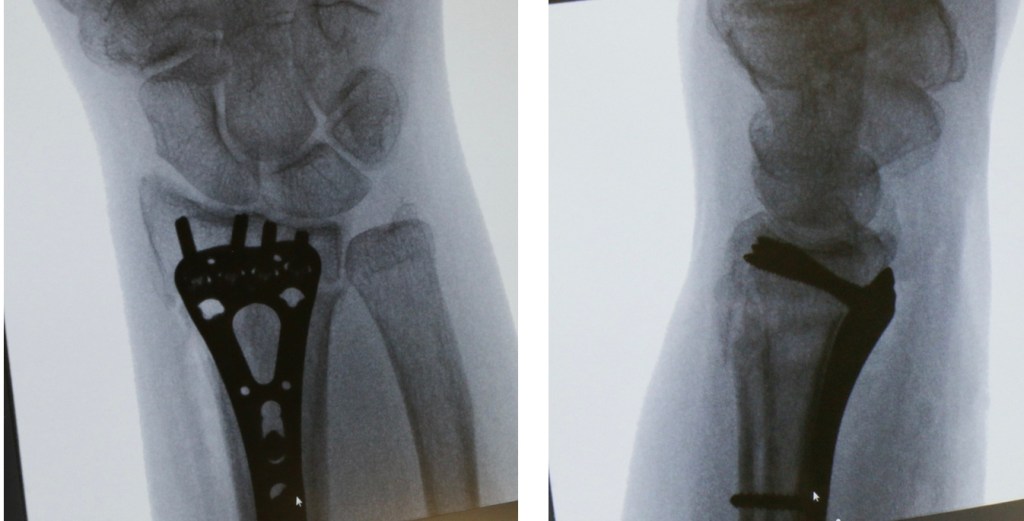

– An operation. At operation, the surgeon will again manipulate the bones back into position and fix them there with either some wires (these wires are a bit like barbeque skewers – they are relatively stiff with a pointed end to drill into the bone), or a plate. If a bone plate is used, a wound is made over the palm side of the wrist, and the plate inserted under the muscles and tendons.

A fracture treated with a plate…………

Although surgery stabilises the bones and usually allows early movement, there are risks involved with surgery, and you can read more about these here. Although the surgeon will aim for a perfect position of the bones, this is not always achieved, and occasionally the fixation fails to hold the position of the bones. Late problems associated with the use of bone plates include tendon irritation or rupture, and the risks and benefits should be discussed with the surgeon before having this type of operation.